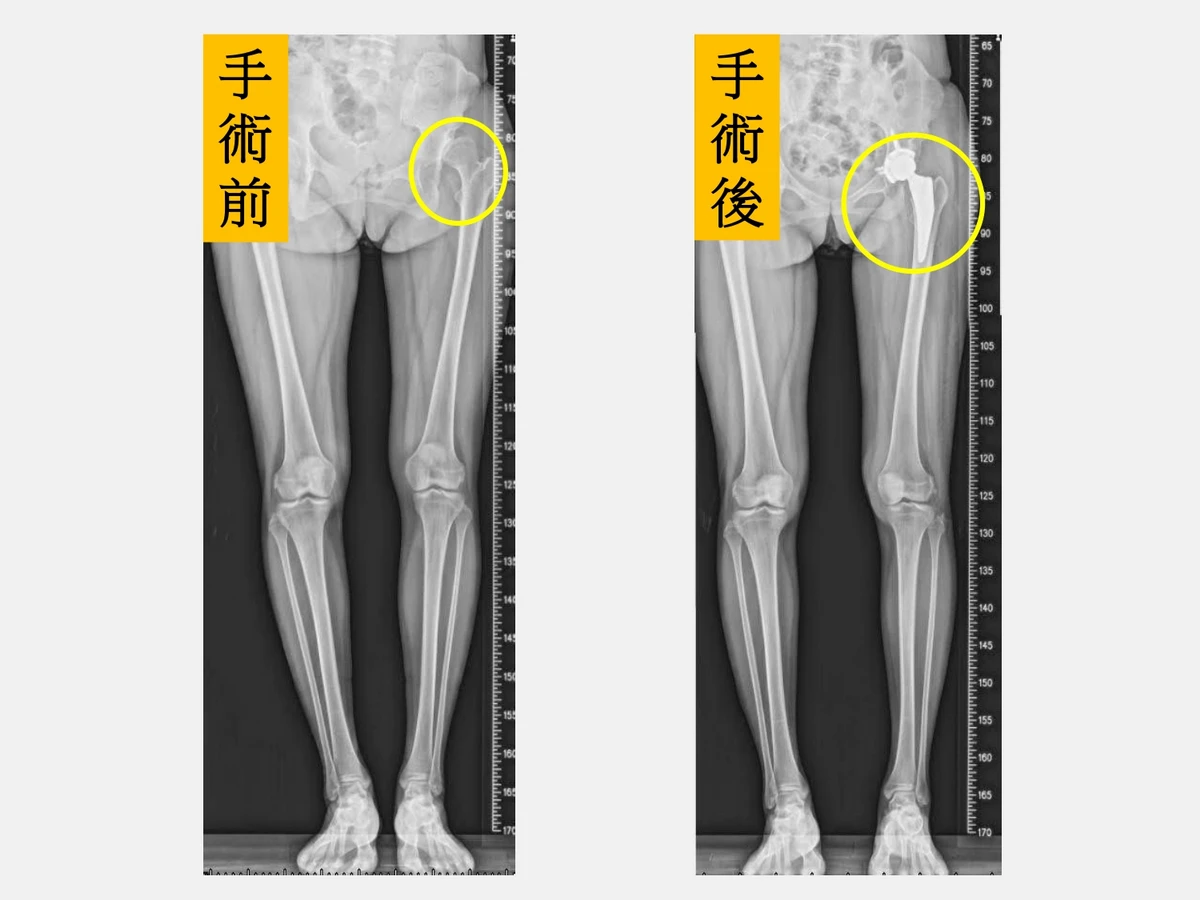

髖關節發育不良」(Developmental Dysplasia of the Hip,DDH)是指股骨頭與髖臼在成長發育過程中未能形成良好穩定的結構,造成髖關節從不穩定到脫位不等的情況。長期下來關節受力不均,會加速軟骨磨損與退化,進而引發早期退化性髖關節炎,常見症狀包括疼痛、僵硬、跛行及長短腳等,嚴重影響生活品質。

仁愛長庚合作聯盟醫院骨科部長黃贊文指出,因髖關節發育不良導致的髖關節炎多好發於40~55歲,且以女性居多。若在兒童時期就診斷出來,可進行髖關節截骨矯正手術;若成年後才發現,可進行截骨矯正手術延緩人工關節置換的時程;但若病情已進展到末期,則建議直接安排人工髖關節置換手術。

「微創正前開髖關節置換手術」術後疼痛減輕,恢復速度較快,行走步態也更穩定。(圖片來源:仁愛長庚合醫院)